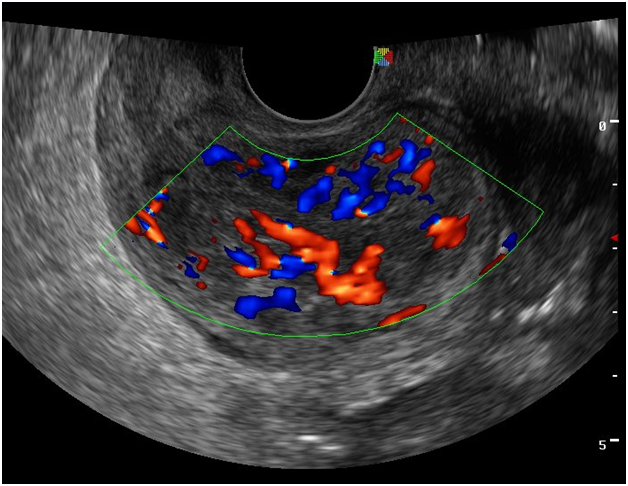

In Taiwan, Wang et al.7 studied 164 out of 3058 culture‒confirmed TB patients (5.4% prevalence) who fulfilled the criteria for disseminated tuberculosis from January 1995 to December 2004. 87 patients (53%) had underlying co‒morbid conditions such as AIDS, diabetes mellitus, malignancy, end‒stage renal disease, autoimmune disease, and alcoholism. Within one year of follow‒up, 99 (60.4%) patients were completely treated and 51 (31%) died, 10 (6.1%) were under treatment and 4 (2.4%) were lost. Poor prognosis factors reflect the severity of TB or the underlying diseases, and include albumin <3.5 g/dL, total bilirubin >1.0 mg/dL, creatinine >1.5 mg/dL and delayed anti‒tuberculosis treatment. This patient had positive AFB smears from all over her body (lungs, urine, stool, pelvis, bone marrow) – suggesting an immuno compromised state such as HIV/AIDS or a person with malignancy or diabetes mellitus. However, the result of HIV screening for this patient was nonreactive and her blood sugar levels were with normal limits. Patients with disseminated tuberculosis have varied presentations which may be lethal if detection is delayed, including pancytopenia,8 hemophagocytic syndrome,9,11 bone marrow necrosis,13 disseminated intravascular coagulation,10 isolated thrombocytopenia.14 Disseminated tuberculosis is treated with quadruple anti‒Koch’s medications, under the DOTS strategy. Interestingly, although the current recommendation is a six‒month treatment regimen for disseminated TB, patients with disseminated tuberculosis are treated for a minimum of 12 months in Saudi Arabia.15 The same is true for our section. However, anti‒tuberculosis medications do have its inherent risks and complications. Petechial rash may suggest thrombocytopenia in patients taking rifampicin.4 The platelet count was checked immediately in our patient and since it was initially low, rifampicin hypersensitivity was identified as the cause. The medications were stopped and hematologic disturbances were corrected prior to resuming the medications. The plan was to restart the medications one by one at intervals of 2‒3 days once the rash improved. However, since there was no observed improvement despite cessation of the medications, a primary hematologic disorder was considered (Figures 11‒14).

Figure 11 Color flow mapping and Doppler studies of the uterus show abundant vascularity.